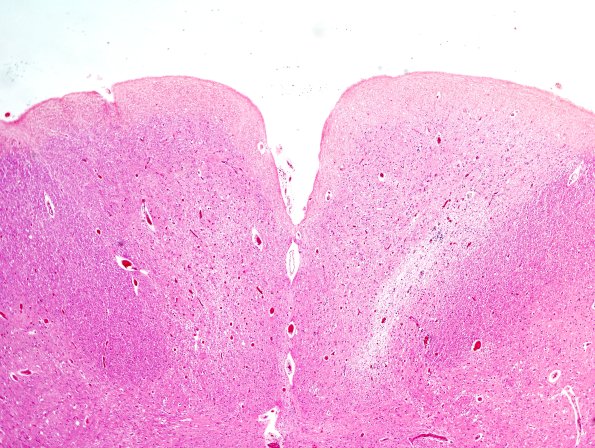

The left gracile nucleus also shows a degree of pallor, although less than the right nucleus. (H&E)